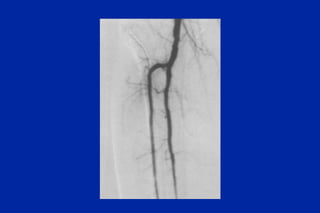

Este documento resume los principales tipos y técnicas de angiografía. Describe brevemente la angiografía, arteriografía, flebografía y linfografía, así como las técnicas de contraste y materiales utilizados. También explica los principales accesos vasculares, la técnica de Seldinger, la angiografía por sustracción digital y algunas técnicas endovasculares comunes.